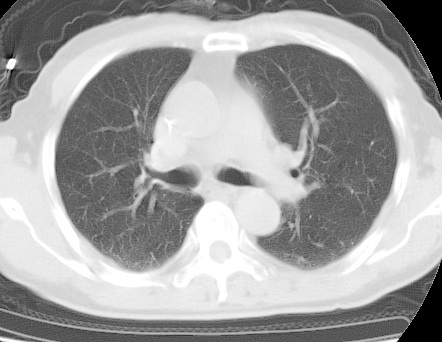

标题: CT24032:男65岁,咳嗽,吸烟20余年,无发热,咳痰 [打印本页]

标题: CT24032:男65岁,咳嗽,吸烟20余年,无发热,咳痰

考虑右肺中叶不张,请大家发表意见

右肺中叶不张、肺门轮廓增大,占位不除外;建议增强,必要时支气管镜详查。

右肺中叶不张,中叶支气管开口不清,建议支气管镜检查。

右肺中叶支气管闭塞,中叶肺不张,右侧肺门见肿块影。中心型肺癌的可能大。建议支气管镜检查。

右中叶体积明显缩小,且其支气管未显示,先考虑:中心型肺癌班右中叶肺不张。

建议:支气管镜检查。

考虑右肺中叶中央型肺癌并右肺中叶肺不张;建议:行纤支镜检查。

右肺门旁类圆形肿块影,右肺中叶不张,建议纤支镜检查。

1右肺门旁类圆形肿块影,右肺中叶不张,建议纤支镜检查

2右侧胸膜增厚,右侧叶间胸膜区钙化

3右肺下叶小囊状透亮影考虑肺气肿

平片就可以诊断右肺中叶不张,做CT就是要找原因!中叶支气管开口不清,建议支气管镜检查。